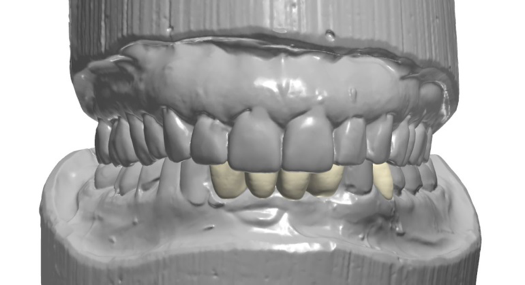

Figure 6 and Figure 7 depict a mature smile with many implant restorations. An analog impression was sent to the laboratory. The impression was scanned by the laboratory, a model was created virtually, and the implant dimensions and position were defined. The 3D surgical guide was fabricated (Figure 8), allowing the patient to receive his therapy swiftly and predictably. Tooth No. 8 was extracted, and the implant was placed and immediately loaded with an acrylic provisional treatment crown (Figure 9). The screw-retained treatment crown was fabricated in-office from a previously completed diagnostic wax-up.

After 4 months of healing and integration of the bone around the implant, the digital workflow was initiated to develop the abutment and treatment plan. Another analog impression was made with an impression post and polyvinyl impression. The laboratory scanned the impression and digitized it to create the emergence profile of the milled titanium abutment and the final restoration (Figure 10 and Figure 11). The patient had a considerably thick soft-tissue profile, allowing a milled titanium abutment. The decision to use a titanium abutment was based on the patient's occlusion and propensity to fracture teeth or restorations. The virtual model was gray because the scanner does not recognize the color of the analog impression. The virtual final abutment and crown were approved and fabrication completed. The final restoration met the patient's esthetic values and his ability to function (Figure 12 and Figure 13).

Fig 8. 3D-printed surgical guide.

Figure 8